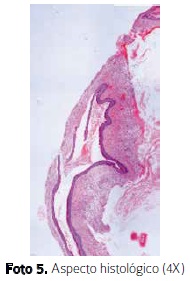

Se encuentra contenido líquido, seroso, gránulos de colesterol y paredes óseas delgadas. Se coloca tubo hemovac para drenaje y se envía muestra a patología. Microscópicamente se observa como una lesión quística revestida por epitelio escamoso estratificado con queratinización y paraqueratosis. La pared, con tejido fibroconectivo, presenta proliferación vascular e infiltrado agudo y crónico y una luz ocupada por queratina. Se establece diagnostico de queratoquiste odontogénico. (Foto 5)